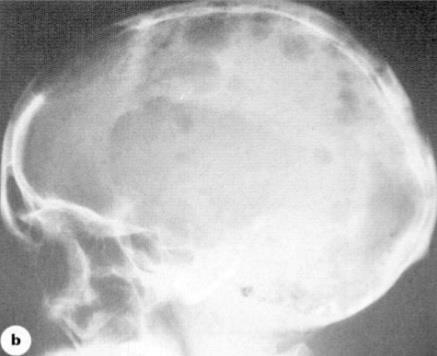

Myeloma Cells Can Produce Myeloma Protein Continually: Detectable in Plasma and Urine

Note: Some patients have nonsecretory disease that does not produce detectable myeloma protein.

17

Understanding Your Test Results, International Myeloma Foundation 2018.

Bone marrow Normal Myeloma Albumin alpha-1 alpha-2 beta gamma Myeloma